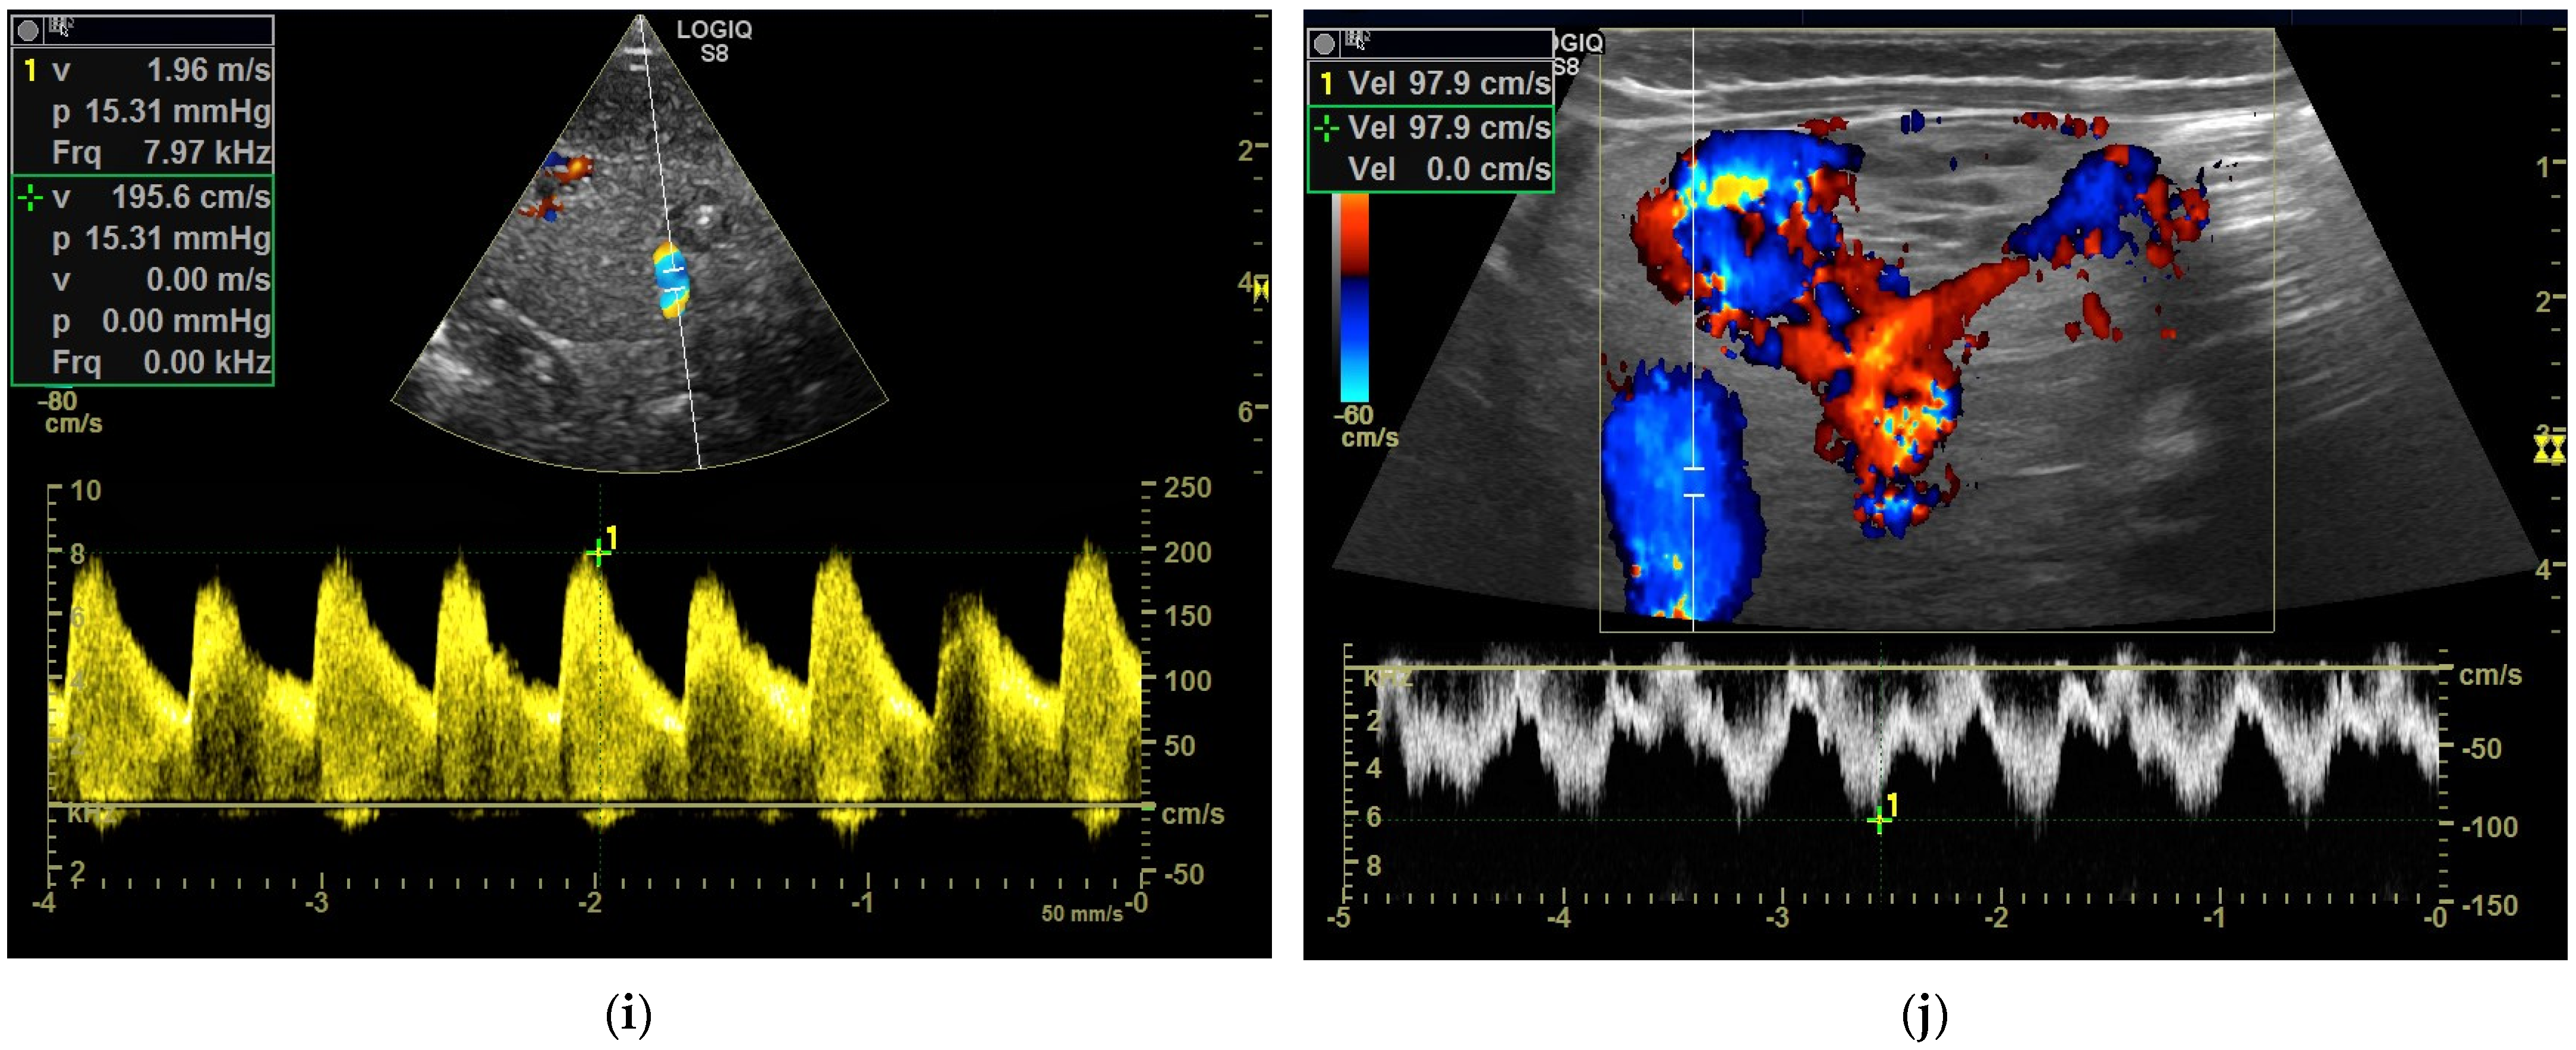

Figure 3.

Hemangioendothelioma in a 1-month-old infant. A cystic mass with a maximum diameter of 4 cm in liver segment IV with blurred borders and calcifications with dorsal acoustic shadow (a–e). Evidence of increased vascularization on color Doppler (f). Feeder artery with inflow from the hepatic artery and venous outflow via the markedly dilated left hepatic vein (g). Increased flow velocities in the coeliac trunk and hepatic artery (h,i). Outflowing left hepatic vein with arterialized flow profile and increased flow velocities (j).